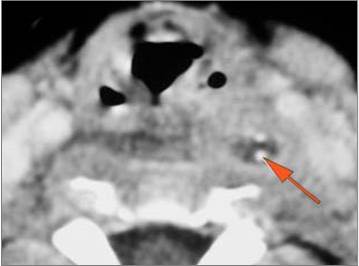

9 month old male presenting to the emergency room with poor feeding, fever, respiratory distress and possible retropharyngeal abscess or suppurative retropharyngeal adenitis.Exam

| Retropharyngeal Lymph Nodes | Correct Answer | Your Answer |

|---|---|---|

There is reactive retropharyngeal lymphadenopathy. |

Yes | NA |

There is suppurative retropharyngeal lymphadenopathy. |

If there is suppurative retropharyngeal adenopathy what is the maximum short axis dimension of the largest suppurative node. Measurement |

< 2cm | NA |

There is edema/abscess within the adjacent parapharyngeal and retropharyngeal spaces. |

Impression

Expert Answer

Pharyngitis with suppurative retropharyngeal adenitis.